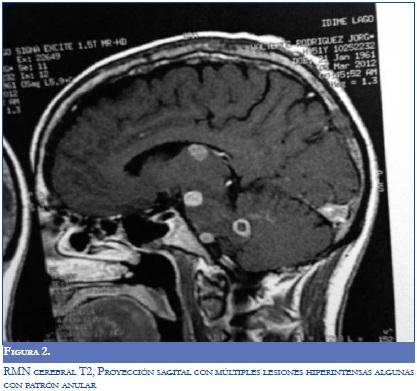

Se ordenó RMN que demostró múltiples lesiones nodulares iso e hipointensas en T1 que aumentaron su intensidad en FLAIR y T2 algunas eran captantes y de patrón anular, de tamaño variable asociadas a edema y con efecto compresivo local, las más evidentes estaban localizadas en ambos hemisferios cerebrales, en el dorso del tálamo izquierdo y en región pontomesencefálica anterior izquierda y en el aspecto anteromedial del hemisferio cerebeloso derecho (Figura 2).

Hay que tener en cuenta que solo en una cuarta parte de los casos los síntomas neurológicos preceden a la sintomatología pulmonar y de mucosas, por lo que el patrón neroimaginológico con presencia de lesiones hipodensas o hipointensas en la TC y la RM con refuerzo perilesional del contrate y edema vasogénico o en algunas ocasiones presencia de nodularidad dentro de estas cavidades que refuerzan con el medio de contraste sugieren el compromiso pseudotumoral de la infección. Según diferentes series de casos el 65% de las veces el compromiso es multilesional y en 35% son únicas (20,21), cuando no hay compromiso pseudotumoral y la clínica es de meningoencefalitis se puede encontrar realce meníngeo en la imagen de RMN. Cabe aclarar que este tipo de lesiones también pueden estar presentes en otras infecciones que afectan el sistema nervioso central como en tuberculosis, cisticercosis y toxoplasmosis. Existen otros tipos de neuroimagenes funcionales como la espectroscopia o la tomografía por emisión de positrones los cuales pueden orientar el diagnóstico diferencial en presencia de abscesos cerebrales versus compromiso neoplásico (22,23), sin embargo hay que resaltar que el diagnóstico de NPCM se hace de manera microbiológica e histopatológica mediante biopsia por estereotaxia de la lesiones cerebrales o por cultivo del líquido cefalorraquídeo (10,24).